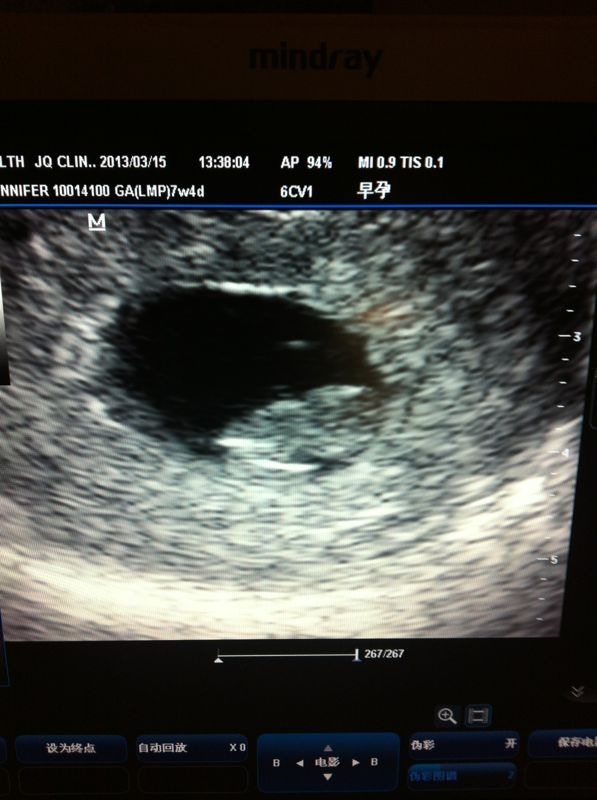

While the this year has brought us many wonderful blessings, the greatest, without a doubt, is the little girl I have growing in my belly! Isla Grace (pronounced “eye-la”) is due October 25th and we cannot wait to meet our little pumpkin! She is undoubtedly the greatest contributing factor to my lack of blogging, as the morning sickness that often accompanies the first trimester of pregnancy nearly wiped me out. Once you miss a few months, the ability to catch up while working and moving is nearly impossible. But, now it is summer, and we have glorious, beautiful free time! So, here I will do my best to recount the first 22 weeks of pregnancy. (HA! Apparently not, as it is now August and we are 30 weeks along… good try, me!)

12 week appt– saw Baby on the ultrasound, shocked that it looked like a real little person! Giggled at the profile and developed nose (of course! It is our baby after all.). Baby was flailing about, but refused to show the doctor the back of its neck, which she wanted to see as part of the chromosomal disorder screening. We took a break, went and had a lovely Thai lunch and walked around in the sunshine for an hour. Went back and baby was in a better position for the Down’s test. All looked good from measurements. Later got a call that all blood work came back looking great as well. Hooray! After the appointment we excitedly walked to Starbucks so that we could use their internet and announce our big news to the world- a much anticipated event!!! Starbucks was packed, Internet was completely difficult, but we eventually posted our news. In the process of all the hubbub I managed to leave without our ultrasound photo… so disappointed=(.

16 week appt– Didn’t expect to get an ultrasound, but Dr. Lu Ferguson asked if we wanted to know the baby’s gender and then whisked us away to the ultrasound room. We were giddy! As she set up the ultrasound, Dr. Lu Ferguson asked what we thought we were having. I explained boy and the pencil test, and Isaac had thought it was a girl. But, just as last time, Baby was not interested in cooperating and had his/her back turned to us the entire time. Dr even switched on the 4D ultrasound, but Baby wouldn’t show us anything but its backside… cutest back of the head, little ears, neck and shoulders we’ve ever seen!

Tried inverting the table and propping my hips up on my hands, but Baby still wasn’t interested in showing us anything back the back of its head. Dr. Lu Ferguson suggested the internal ultrasound- not glamorous, but at that point I was so eager to find out that I didn’t care. Started looking and sure enough baby’s legs were glued together. Modest! Dr. Lu Ferguson and the ultrasound tech looked at the baby’s pelvis for a while, murmuring in agreement with one another. For a split second Dr. Lu Ferguson got a peek at the baby’s underside. “Oh, it’s a girl.” She said, sounding almost surprised herself. Rewinding the feed and freezing the image she looked again and said, “Yep, that’s a girl.” Isaac, with a surprised but happy smile, lips pursed, grabbed my foot and looked back at me. I was floored. Dr spent a few more moments examining the ultrasound and said she was pretty certain- “maybe 80%” but not to buy everything just yet as we would confirm at the 20 week appointment.

20 week appointment– Baby is healthy and confirmed to be a girl. Isla Grace, our baby GIRL!!!